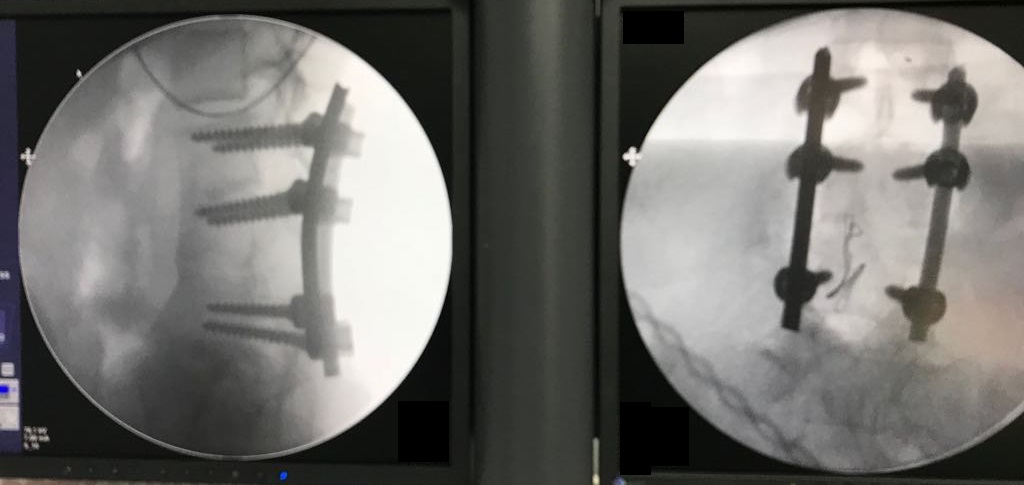

Lomber osteotomi yapıldı.

Ameliyat Görüntüleri